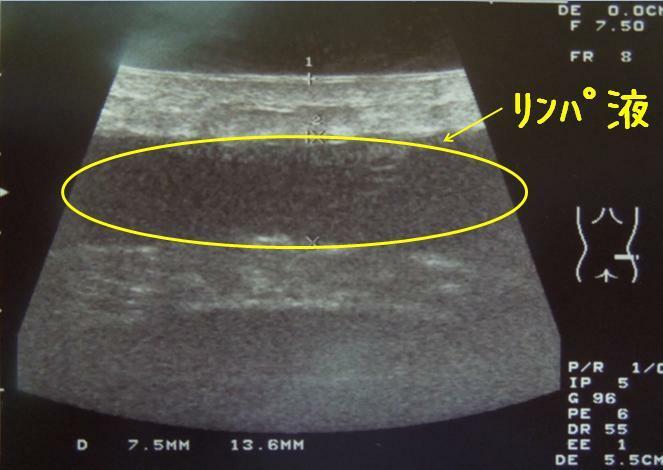

写真は、左ウエスト部の

超音波エコーの画像ですが、

写真中央部に、帯状に黒く写っている部分が

あるのがわかると思います。

これは、術前に皮下脂肪があった場所に、

液体(リンパ液)が溜まっていることを示しています

B様の場合、左のウエストだけに、

最大 14mmの厚さで液体が貯留していて

量が多いことが予想できました。